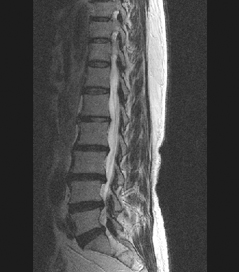

HLD on L-spine, Lt. L5 & S1 Radiculopathy

64세 여자환자는 2개월 전부터 요통과 다리 바깥쪽과 발등, 종아리 뒤쪽으로 저린 감각이 심해져서 개인병원에 들러 평가 및 물리치료를 받았으나 별다른 호전이 없고, 1주일 전부터는 허리를 숙이거나 물건을 들 때, 오래 걸을 때 통증이 더 심해져서 본원을 방문하였다. 12년전 집안일을 심하게 하고 난 후부터 간헐적인 요통을 발생하였으며, 별다른 치료 없이 지냈으며, 4년전 무거운 물건 들고 난 후 심하게 요통과 둔부의 통증까지 발생하여 MRI 촬영상 L1-2, L3-4-5, L5-S1 HNP와 Lt. L4 & both L5 nerve compression, Lt. S1 nerve compression 진단받고 Epidural steroid injection을 받고 통증 경감되었고, 간헐적으로 통증이 발생하였으나 별다른 치료 없이 헬스클럽에서 지속적인 운동으로 관리하였다.

• 척추 방사선 사진1